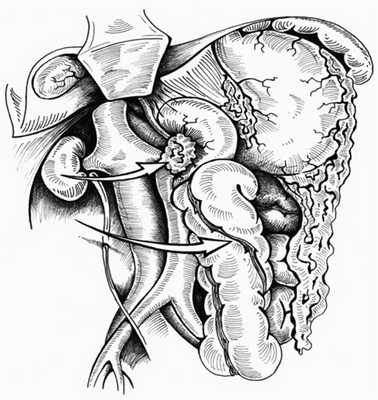

1. Левосторонний доступ (прием Mattox [4]) применяем при локализации забрюшинного кровоизлияния слева от диафрагмы до корня брыжейки поперечной ободочной кишки. Этот доступ дает возможность выделить и осмотреть аорту от диафрагмы до инфраренального отдела, чревный ствол, верхнюю брыжеечную и левую почечную артерии, селезенку, хвост и тело поджелудочной железы, нисходящую ободочную кишку, селезеночную артерию, левую почку и левый мочеточник. Схема левостороннего доступа представлена на рис. 1 (см. и далее).

Рис. 1. Схема левостороннего доступа. 1 — чревный ствол, 2 — верхняя брыжеечная артерия, 3 — левая почечная артерия. Стрелка — направление смещения органов.